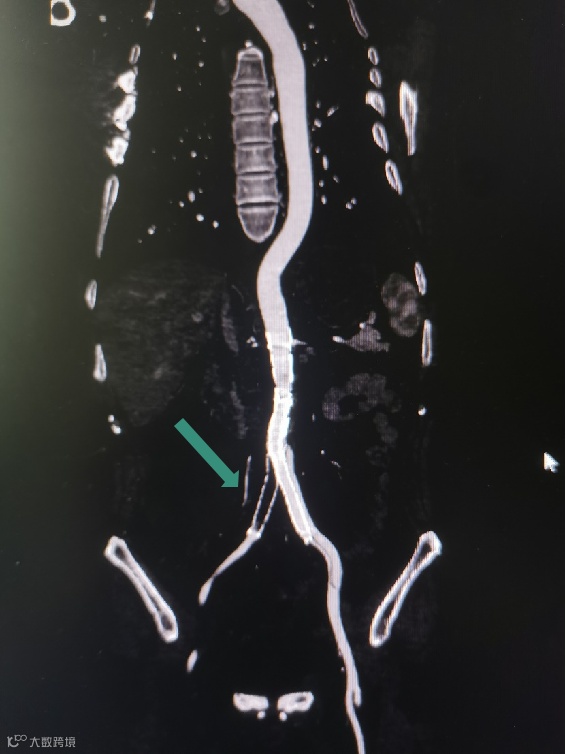

Separator With Aspiration catheter for Mechanical Thrombectomy(MT)【分离器辅助导管抽吸技术】:旨在提高整体系统的抽吸效率和治疗安全性,快速帮助血栓清除。

1)抽吸导管头端堵管,分离器可以快速疏通导管,降低撤管冲洗的频率。

2)针对大负荷血栓或亚急性血栓,分离器辅助下抽吸能提升整体系统抽吸效率,缩短手术时间。

手术过程